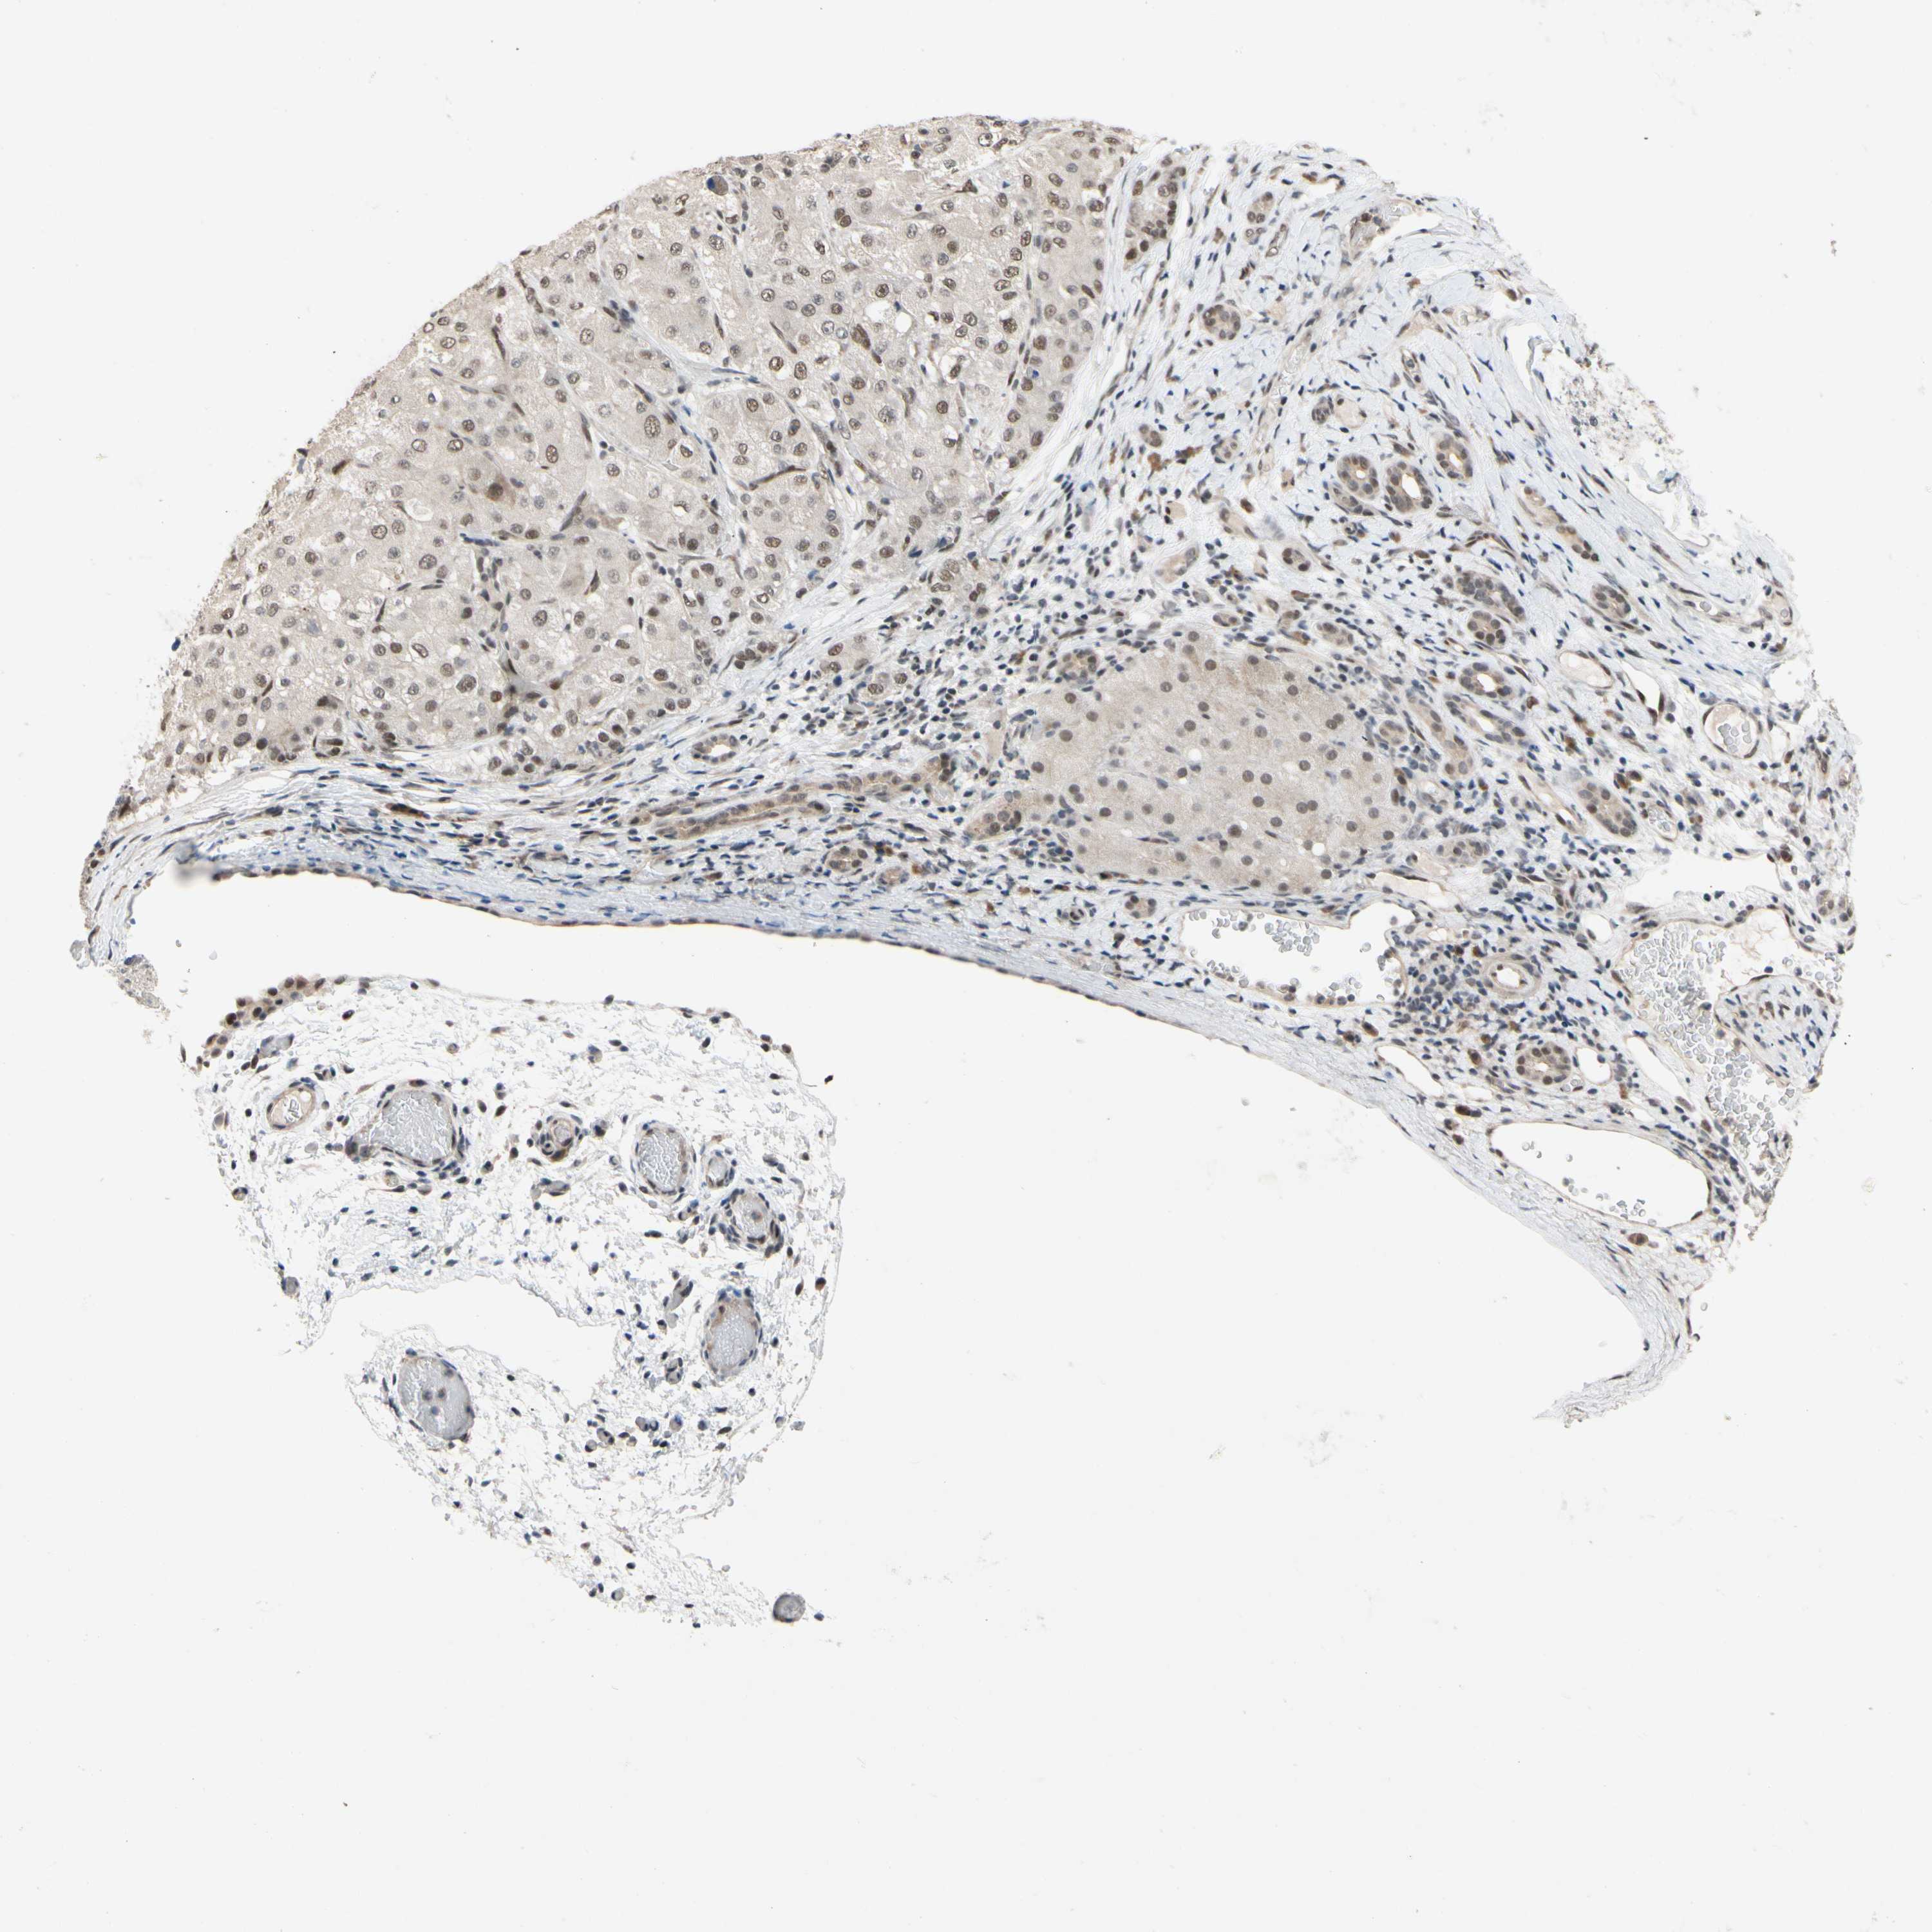

LIVER CANCER - Protein expressioni

A mouse-over function shows sample information and annotation data. Click on an image to view it in a full screen mode. Samples can be filtered based on level of antibody staining by selecting one or several of the following categories: high, medium, low and not detected. The assay and annotation is described here.

Note that samples used for immunohistochemistry by the Human Protein Atlas do not correspond to samples in the TCGA dataset.

Antibody stainingi

Antibody staining in the annotated cell types in the current human tissue is reported as not detected, low, medium, or high, based on conventional immunohistochemistry profiling in selected tissues. This score is based on the combination of the staining intensity and fraction of stained cells.

Each image is clickable and will lead to virtual microscopy that enables deeper exploration of all samples and also displays staining intensity scores, fraction scores and subcellular localization as well as patient and tissue information for each sample.

Antibody HPA008599

Antibody CAB031484

Staining

High

Medium

Low

Not detected

Intensity

Strong

Moderate

Weak

Negative

Quantity

>75%

75%-25%

<25%

None

Location

Nuclear

Cytoplasmic/membranous

Cytoplasmic/membranous,nuclear

Cholangiocarcinoma

Carcinoma, Hepatocellular, NOS